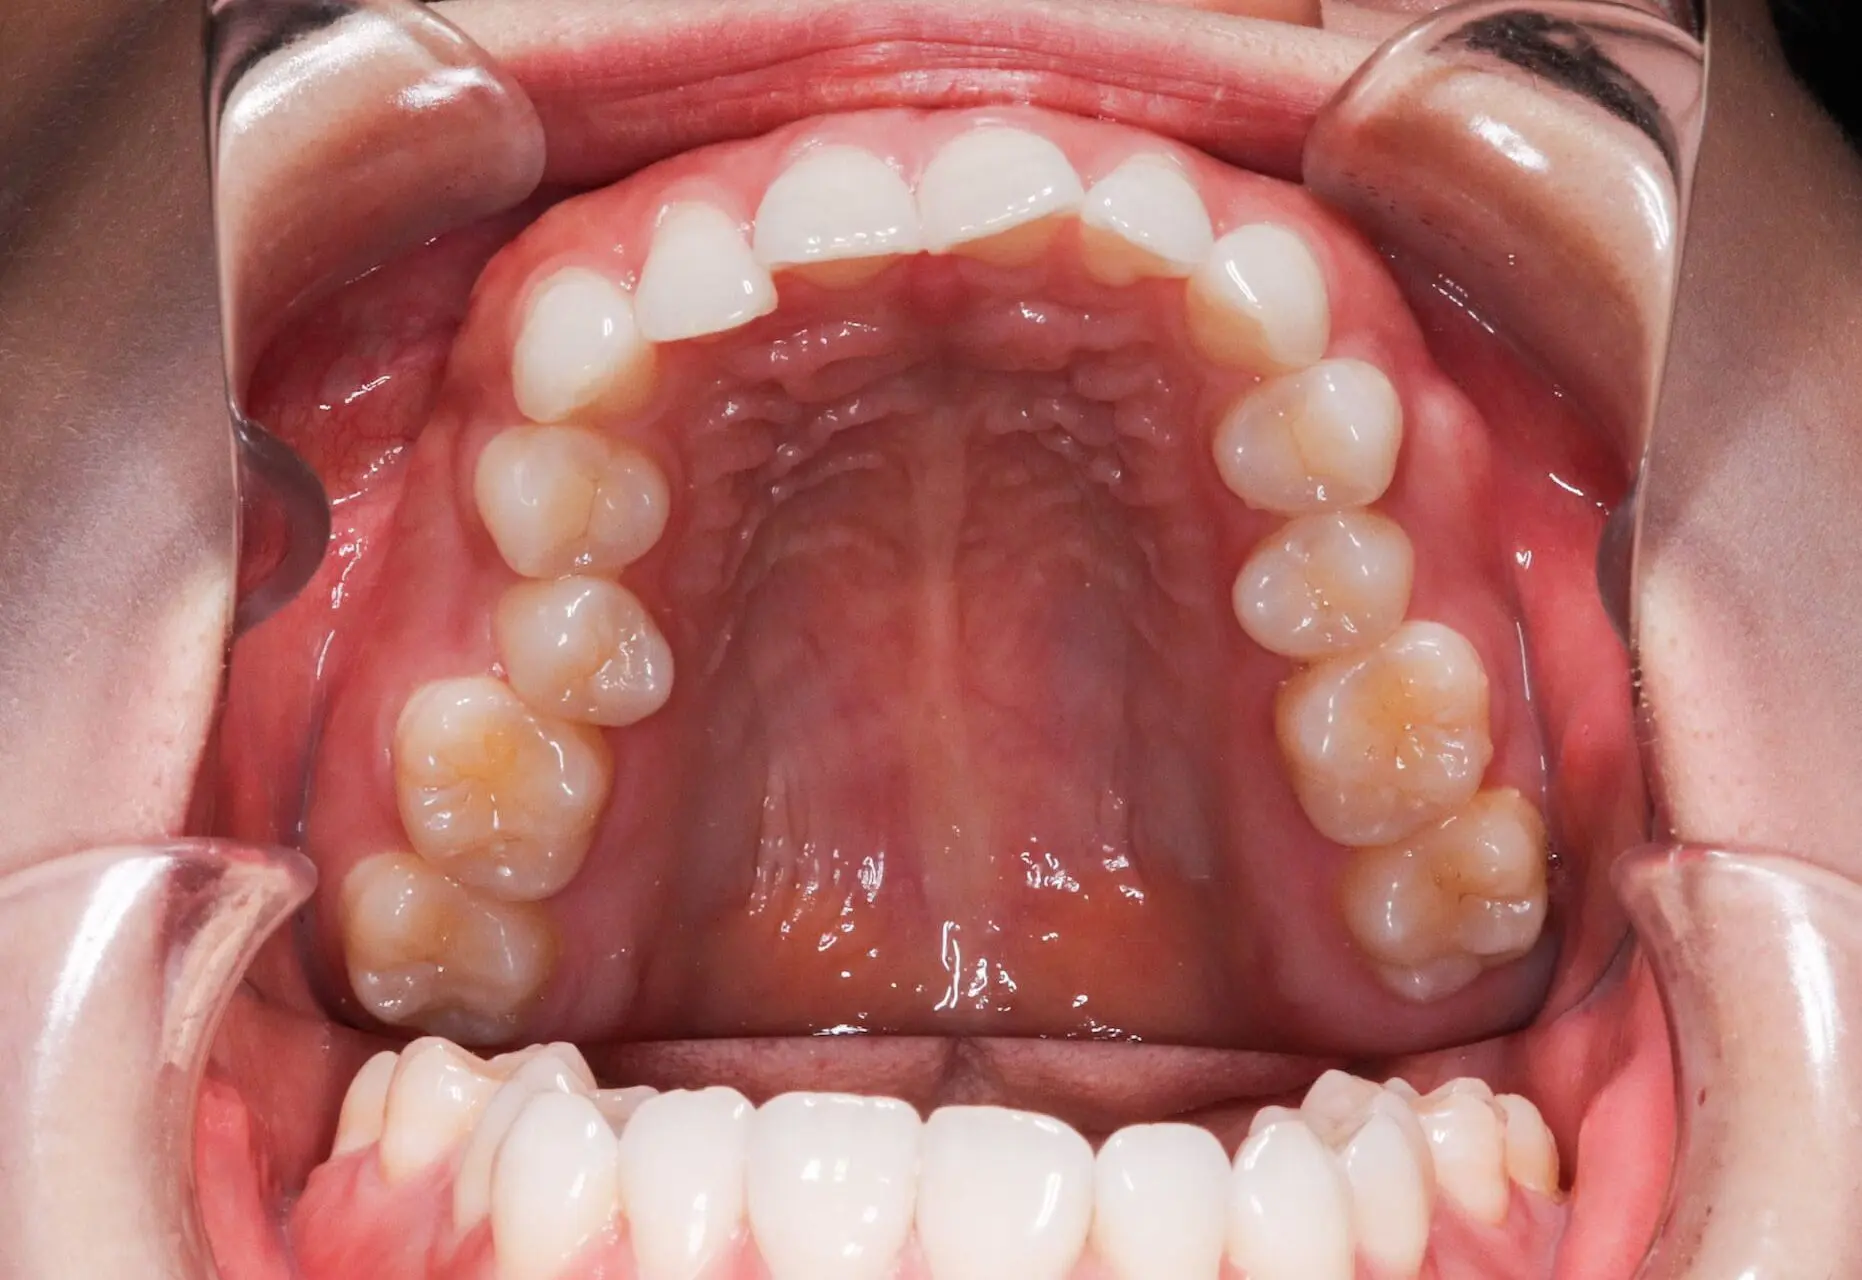

Crowding

Before